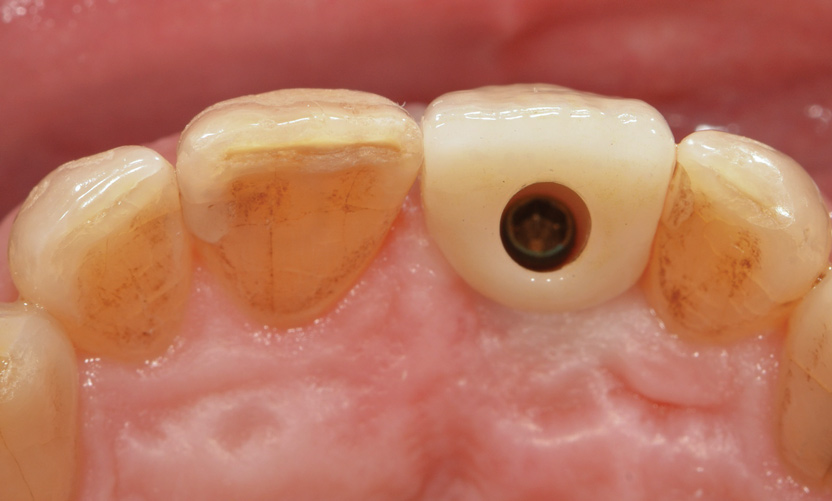

Fig 1. Incisal view (clinical) with impression coping in place demonstrating buccal angulation of implant.

Figure 1